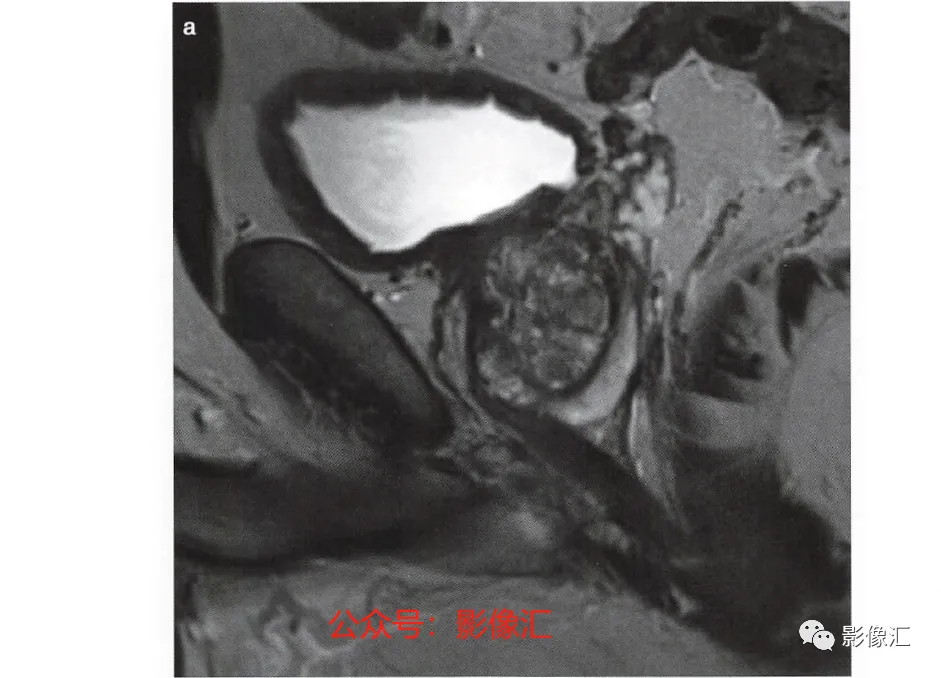

2. 正中矢状面(图2.20)